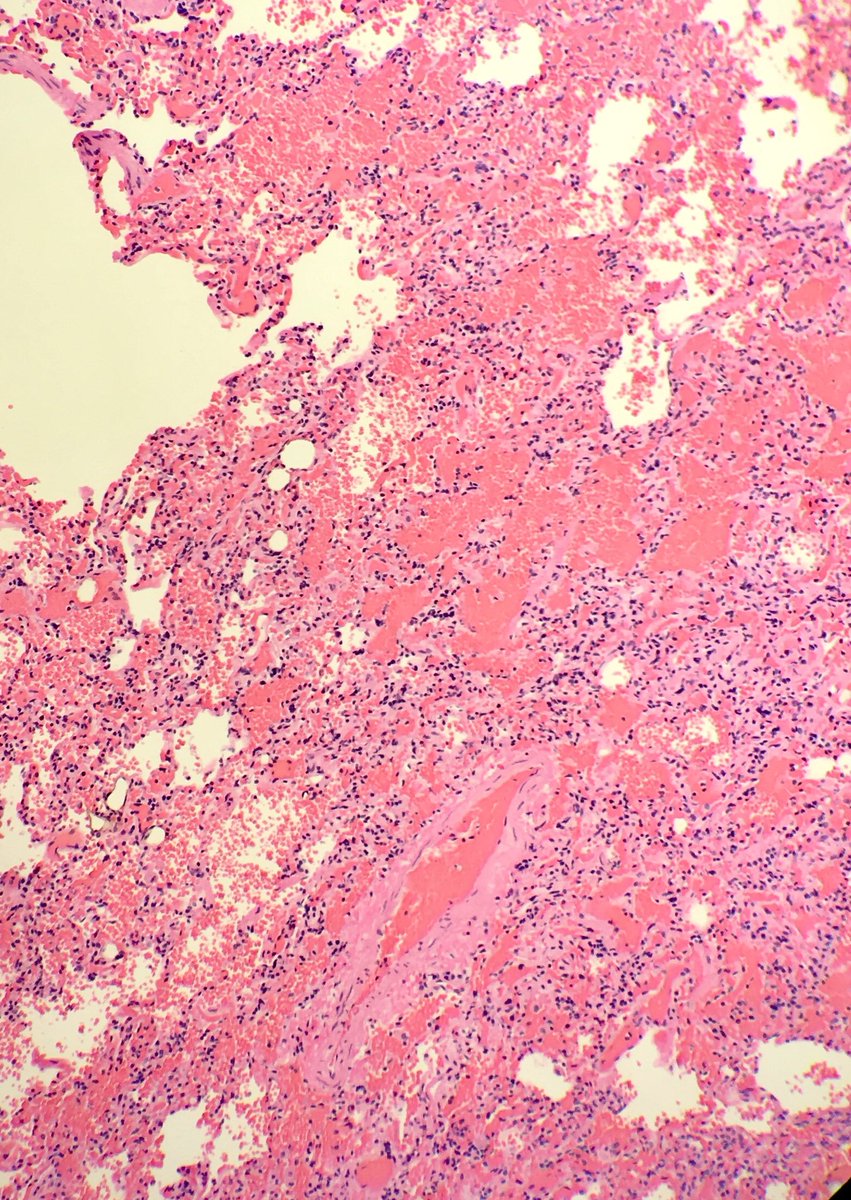

Fat emboli: ~85% of trauma patients w/ attempted resuscitation have fat emboli at autopsy. Why else? #pulmonarypath #forensicpath

seattlequinns's tweet image. Fat emboli: ~85% of trauma patients w/ attempted resuscitation have fat emboli at autopsy. Why else? #pulmonarypath #forensicpath